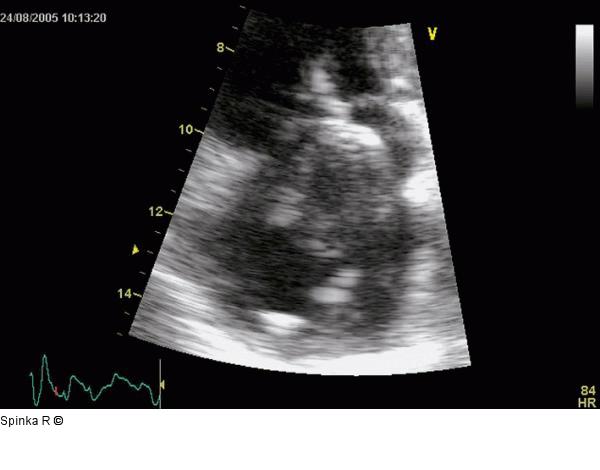

Abbildung 3: Rechtsatriale Thrombose nach 2-Kammer-Schrittmacherimplantation Transthorakale Darstellung der regressiven Veränderung nach mehrwöchiger Therapie mit oralen Antikoagulantien. |

Transthorakale Darstellung der regressiven Veränderung nach mehrwöchiger Therapie mit oralen Antikoagulantien. |